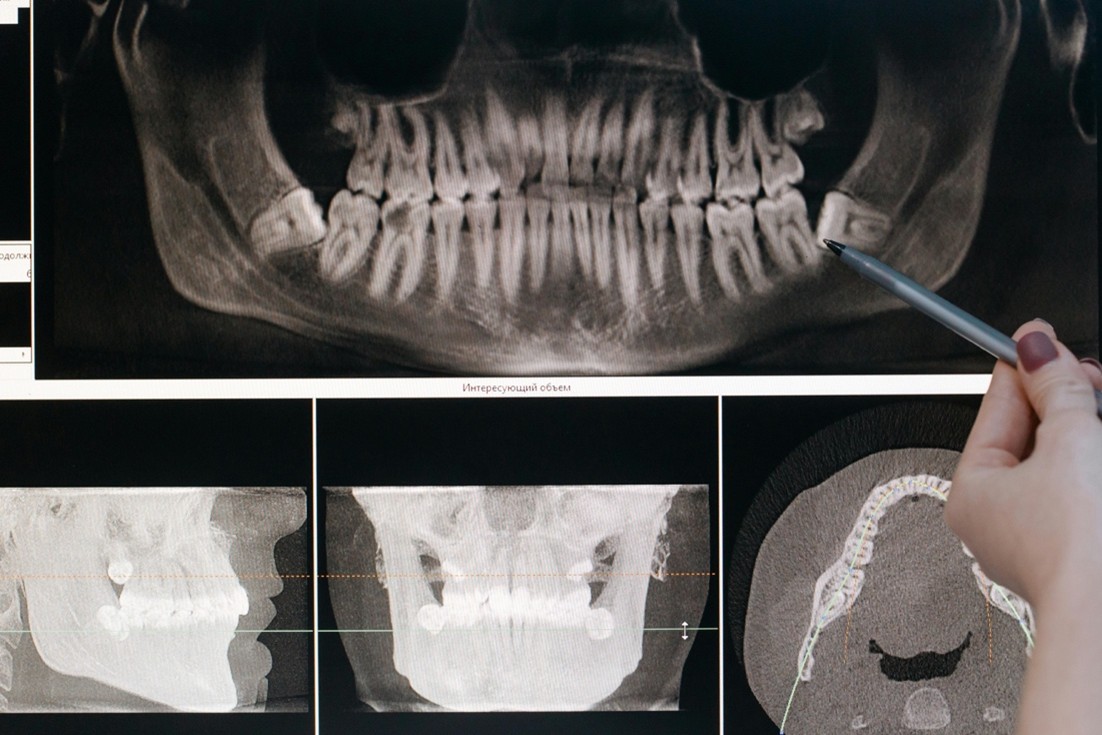

Implant Innovations: Transforming Smiles with Single Implants